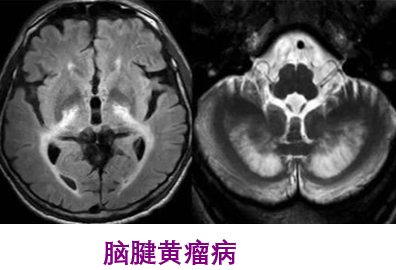

腦腱黃瘤?。–TX )簡介

一、概述腦腱黃瘤病(CTX)是一種罕見的常染色體隱性遺傳代謝性疾病,是CYP27A1基因突變造成固醇﹣27羥化酶缺陷致病。固醇-27羥化酶缺乏,膽固醇合成膽汁酸受阻,引起不同組織膽固醇代謝障礙。由于體內(nèi)沉積的膽甾烷醇和膽固醇有神經(jīng)毒性作用,導(dǎo)致中樞-周圍神經(jīng)系統(tǒng)的廣泛損害,出現(xiàn)癡呆、小腦性共濟失調(diào)、延髓麻痹、進行性下肢疼攣性癱瘓和周圍神經(jīng)病,肌腱黃瘤、青少年白內(nèi)障和早發(fā)的動脈硬化。磁共振檢查可見雙側(cè)小腦齒狀核、小腦白質(zhì)T2高信號,可累及小腦腳、腦干錐體束及內(nèi)側(cè)丘系走行區(qū)、腦室周圍白質(zhì)、胼胝體和基底核區(qū),隨病情進展可出現(xiàn)齒狀核T2低信號,可見小腦萎縮。二、臨床表現(xiàn)CTX在不同年齡人的身上,癥狀表現(xiàn)有所不同,嬰幼發(fā)病的患兒以慢性腹瀉癥狀表現(xiàn);幼年型患二常出現(xiàn)白內(nèi)障;少年至青年型患者,則易于多處肌腱出現(xiàn)脂肪堆積的黃瘤;成人型患者可能表現(xiàn)出退行性中樞病變。1.眼睛白內(nèi)障:約75%患者發(fā)生干10歲前,其余25%常發(fā)生于40歲之后。其它表征有眼瞼黃瘤、視神經(jīng)萎縮、眼球突出。發(fā)生視神經(jīng)盤蒼白者占50%,發(fā)生早發(fā)性視網(wǎng)膜衰老合并視網(wǎng)膜血管硬化者為30%。青少年時期發(fā)生雙眼白內(nèi)障者占90%。2.神經(jīng)系統(tǒng)表現(xiàn)中樞神經(jīng)系統(tǒng)在20-30歲間出現(xiàn)錐體系癥狀者占67%,小腦性共濟失調(diào)占60%,智能低下(20歲后)占57%,癲癇(約50%)與周圍神經(jīng)病各占24%。小腦體征以及錐體外系有肌張力障礙、類帕金森癥狀等;神經(jīng)精神病學(xué)癥狀有幻覺、行為改變、躁動、憂郁等。32%表現(xiàn)為智能發(fā)育遲緩,24%出現(xiàn)步態(tài)異常。神經(jīng)系統(tǒng)癥狀中,錐體系小腦性共濟失調(diào)占60%,智能低下占57%,癲癇與周圍神經(jīng)病各占24%。3.周圍神經(jīng)病變感覺異常、肢體末端肌肉萎縮及高弓足等。4.黃瘤介于20-30歲間。發(fā)生在跟腱、手及手肘伸肌、膝蓋及頸部等處;肌腱黃瘤的發(fā)生率占56%。跟腱腫物邊界清、質(zhì)硬、動度差、輕度壓痛,無搏動感。跟腱MR顯示跟腱顯著增粗,肌腱中有黃色瘤形成。5.心血管早發(fā)的動脈硬化及冠狀動脈疾病。6.胃腸道嬰幼兒慢性腹瀉(最早發(fā)生的癥狀);膽結(jié)石(較少見)。7.提早老化早發(fā)性白內(nèi)障、骨質(zhì)疏松、掉牙、動脈硬化及神經(jīng)損傷性的癡呆等。8.內(nèi)分泌甲狀腺功能低下。9.影像學(xué)表現(xiàn)頭顱MRI典型表現(xiàn)有小腦、側(cè)腦室周圍白質(zhì)、基底節(jié)、腦干對稱性的長T2信號,同時伴有大、小腦萎縮,可見小腦齒狀核軟化及鈣化灶。MRS病灶處乳酸峰及脂質(zhì)峰增高,NAA峰降低。三、化驗檢查1實驗室檢查血漿膽甾烷醇及尿膽汁醇含量異常升高,是診斷CTX的實驗室檢查最有用的指標(biāo)。烷醇含量較正常水平高5~10倍,,血漿膽汁醇含量可較正常水平高500~1000倍。腦脊髓液中膽甾烷醇及載體蛋白β上升;皮膚切片培養(yǎng)細胞、血中及肝中的固醇27-羥化酶活性顯著偏低。2.影像學(xué)檢查顱腦MRI見齒狀核及小腦,大腦白質(zhì)的異堂信號。3.基因檢查CYP27A1基因缺陷率為99%-100%。四、發(fā)病機制本病的可能發(fā)病機制是膽酸合成障礙、膽固醇代謝產(chǎn)物膽甾烷醇異常蓄積。健康人體內(nèi),固醇27-羥化酶催化膽固醇氧化反應(yīng),生成27-羥基膽甾醇,后者再經(jīng)膽固醇-7α-羥化酶(CYP7A1)催化生成膽酸及鵝去氧膽酸(CDCA),是人體生成膽酸的最主要途徑。CTX患者膽固醇27-羥化酶活性不足導(dǎo)致CDCA合成不足,進一步引起膽固醇負反饋調(diào)節(jié)性升高,通過膽固醇-膽酸經(jīng)典代謝途徑,使膽甾烷醇及膽汁醇含量升高,并在多個系統(tǒng)內(nèi)大量堆積而引發(fā)相應(yīng)臨床癥狀。五、遺傳機制本病的致病基因是CYP27A1,該基因位于2號染色體長臂q33-qter。CYP27A1編碼由498個氨基酸組成的固醇27-羥化酶,該基因突變造成固醇27-羥化酶活性大大降低。CYP27A1突變有70余種,其中45%屬錯義突變,20%無義突變,18%剪接突變,4%缺失突變,2%插入突變。超過50%的突變發(fā)生于6號至8號外顯子之間,14%位于2號外顯子,14%位于4號外顯子區(qū)域。:絕大多數(shù)的錯義突變通過影響血紅素結(jié)合位點及腎上腺鐵氧還原蛋白結(jié)合位點,破壞固醇27-羥化酶活性;剪接突變導(dǎo)致mRNA快速變性,使翻譯表達失敗。基因突變類型與臨床表型之間并無相關(guān)性:有相同癥狀患者的CYP27A1突變位置及類型可完全不同,在同一家系不同個體之間,臨床表現(xiàn)也可有很大差異。六、治療本病用補充膽酸治療有效??诜﨏DCA750mg/d可使血漿膽甾烷醇、尿膽汁醇水平恢復(fù)正常,并使患者臨床癥狀明顯改善。